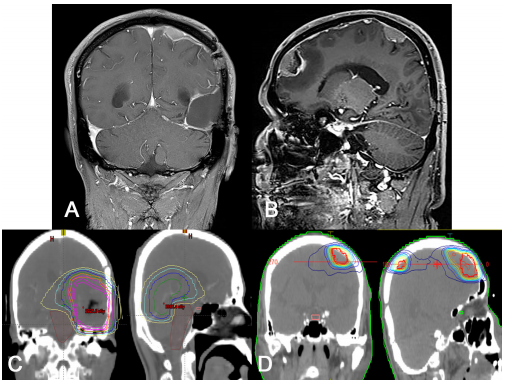

怀疑是胶质瘤,进行了开颅手术和肿瘤全切除术。在手术中,发现一个浸润性肿块侵入硬脑膜,包括窦壁部分。病理诊断为异柠檬酸脱氢酶(IDH)-野生型胶质母细胞瘤,O6甲基鸟嘌呤DNA甲基转移酶(MGMT)启动子甲基化。组织病理学证实硬脑膜肿瘤细胞浸润(图1D-F)。患者同时接受了化疗(60 Gy)和三个周期的辅助TMZ。不幸的是,在术后5个月的随访MRI中发现左侧额叶和顶叶凸部有两处远端脑膜强化病变(图2A、B),患者接受了TMZ加放射治疗(RT,50 Gy)。由于与初始RT计划相比,辐射场没有重叠,因此辐射坏死的可能性很小(图2C,D)。当时,患者间歇性右肩和背部疼痛。进行了胸部和肩部x光检查,但没有具体的放射学发现。

图2. 复发病灶的放射和治疗计划图像。(A,B)Gd增强T1加权MRI显示沿远端硬脑膜有两个增强的硬膜基底肿块。初始病变没有明确的复发。(C,D)初始辐射(C,60Gy)和再辐射(D,50Gy)治疗剂量的计划。两个剂量计划中的辐射场没有明确的重叠